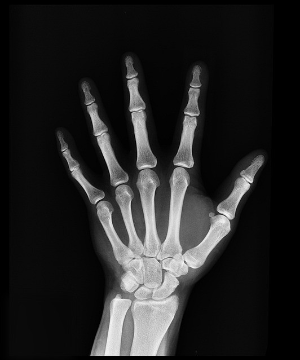

X-ray 사진을 찍어보면, 검게 보이던 성장판이 사라지고 뼈가 하나로 붙은 것처럼 보입니다. 왼쪽의 사진은 실제 제 아이의X-ray 사진입니다. 빨간색 네모 부분이 성장판입니다. 공간이 벌어져있고 얇은 판 같은 금이 보입니다. 하지만 그 옆의 사진은 뼈가 하나로 길게 연결되어 있습니다. 이렇듯 성장판이 모두 뼈로 바뀌고 더 이상 뼈 양 끝에 물렁한 연골이 사라지면 이를두고 '성장판이 닫혔다'고 표현합니다.